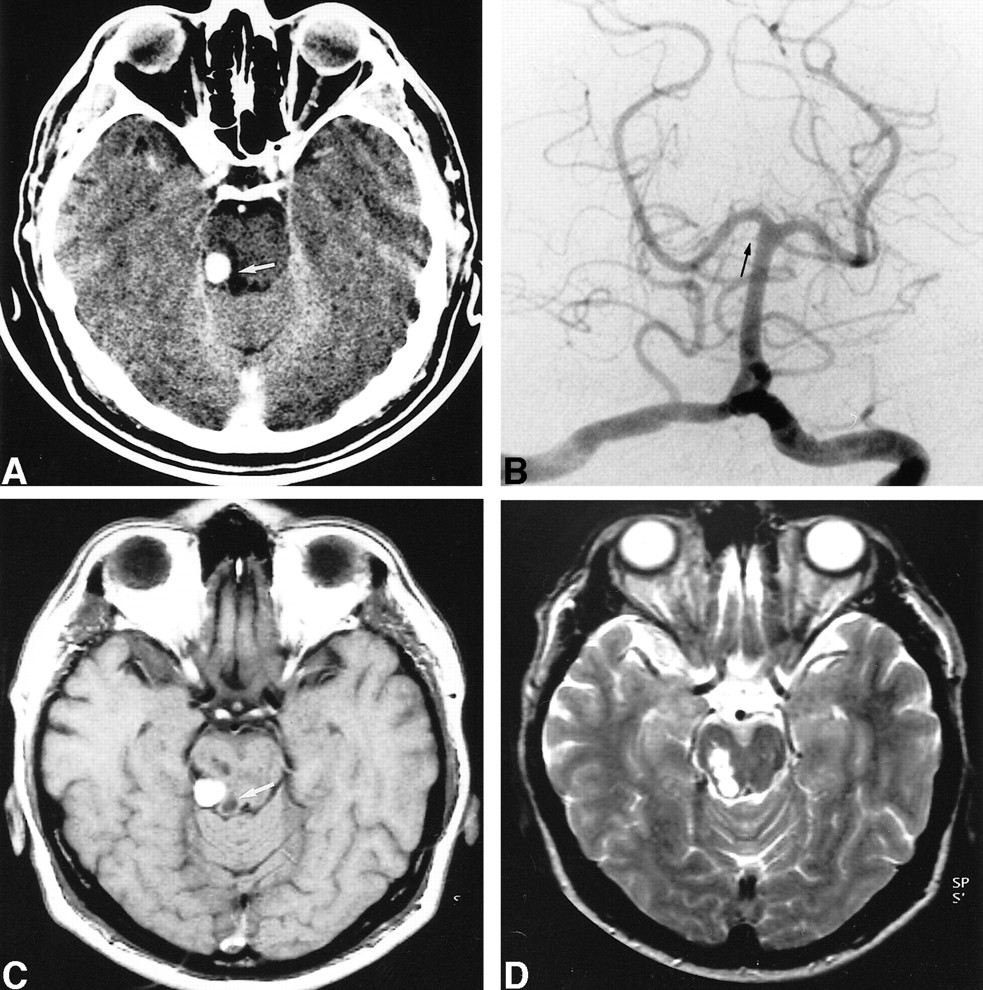

A 49-year-old man presented with a 2-day history of dizziness, slurred speech, right-hand incoordination, diplopia, and mild headache. He had no relevant medical history except for hypertension. There was no history of head trauma, although he reported a precipitous traumatic birth. Physical examination was within normal limits except for right-sided fourth cranial nerve palsy and slight right dysmetria. An initial enhanced CT scan (Fig 2A) showed a 7- × 7-mm round, hyperdense lesion in the ambient cistern suggestive of an aneurysm, and hypodensities in the right cerebellar hemisphere consistent with a recent infarct in the SCA territory. There was no evidence of SAH. MR imaging, performed the day after admission and 1 month later (Fig 2B), disclosed typical signals of blood degradation products within the lesion. Initial MR angiography revealed an absence of flow in the right SCA and no aneurysm, suggesting that the lesion seen on the CT scan was an already thrombosed aneurysm. MR images also showed three small cystic lesions on the right side of the midbrain with no edema or mass effect, as well as a recent infarct in the right SCA territory. Two vertebral angiograms were performed within a 10-day interval. Both angiograms showed complete occlusion of the right SCA at its origin (Fig 2C). Three months later, the patient still had fourth nerve palsy. MR follow-up at 10 months showed disappearance of the mass lesion (Fig 2D).

49-year-old man with 2-day history of dizziness, slurred speech, right-hand incoordination, diplopia, and mild headache.

A, Contrast-enhanced CT scan shows an enhancing well-delineated extraaxial mass in the right ambient cistern. Cystic lesions are also visible within the right midbrain (arrow).

B, Left vertebral selective angiogram (anteroposterior view) shows complete occlusion of the right SCA at its origin (arrow).

C, Unenhanced T1-weighted MR image 1 month after presentation shows high signal intensities consistent with methemoglobin, which was also visible on T2-weighted images (not shown). Cystic lesions of the midbrain are also visible (arrow).

D, T2-weighted MR image 10 months after presentation shows disappearance of the mass. Cystic midbrain lesions are well shown.